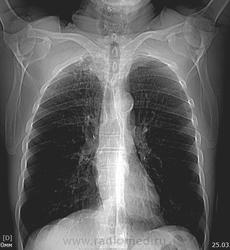

65 лет. Вич - отрицательный. Выявлен при проверочной флюорографии. Последняя флюорография в 2011 г. На контрольное обследование пациента не вызывали. Исходных данных не имею. Жалоб нет. Гемограмма в норме. Выполнена  КТ  органов дыхания. Предполагают туберкулёму, периферический рак? Прошу коллег высказать мнение о возможной природе выявленных изменений. Очень жду. C уважением Nikolas. Ссылка на дайком

Судя по КТ-картине в S1 имеется туберкулема прилегающая к костальной плевре диаметром 2,5см, а вокруг уже имеются мелкие очаги отсева в S1,2 сегментах...

Развил бы "мелкие очаги отсева" в очаговый туберкулез в верхней доле правого легкого в фазе инфильтрации.

Периферический рак никаким боком.

Коллеги. Госпитализирован в ПТД. Буду следить за динамикой процесса в легких на фоне лечения.